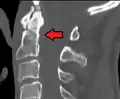

- Type 3 odontoid fracture